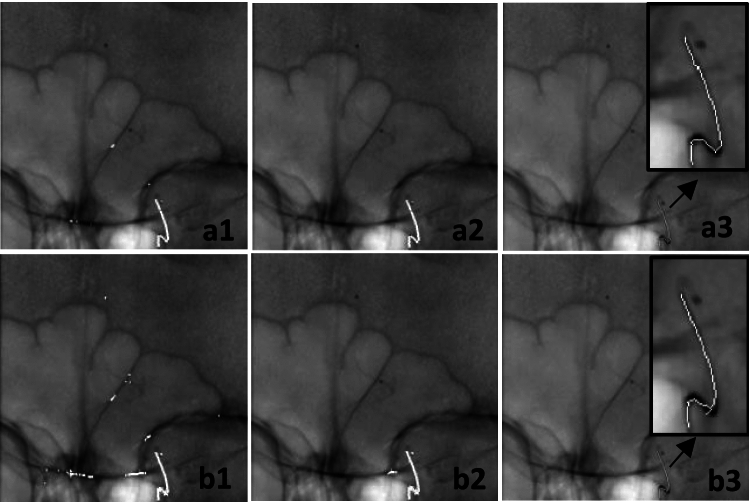

Methods: We propose an online calibration method using image-specific features derived from interventional devices like guidewires and catheters (In the remainder of this paper, the term"catheter" will refer to both catheter and guidewire). The process begins with gantry-recorded data, refined through iterative nonlinear optimization. A machine learning approach detects and segments elongated devices by identifying candidates via thresholding on a weighted sum of curvature, derivative, and high-frequency indicators. An ensemble classifier segments these regions, followed by post-processing to remove false positives, integrating vessel maps, manual correction and identification markers. An interpolation step filling gaps along the catheter.

Results: Among the optimized ensemble classifiers, the one trained on the first frames achieved the best performance, with a specificity of 99.43% and precision of 86.41%. The calibration method was evaluated on three clinical datasets and four phantom angiogram pairs, reducing the mean backprojection error from 4.11 ± 2.61 to 0.15 ± 0.01 mm. Additionally, 3D accuracy analysis showed an average root mean square error of 3.47% relative to the true marker distance.